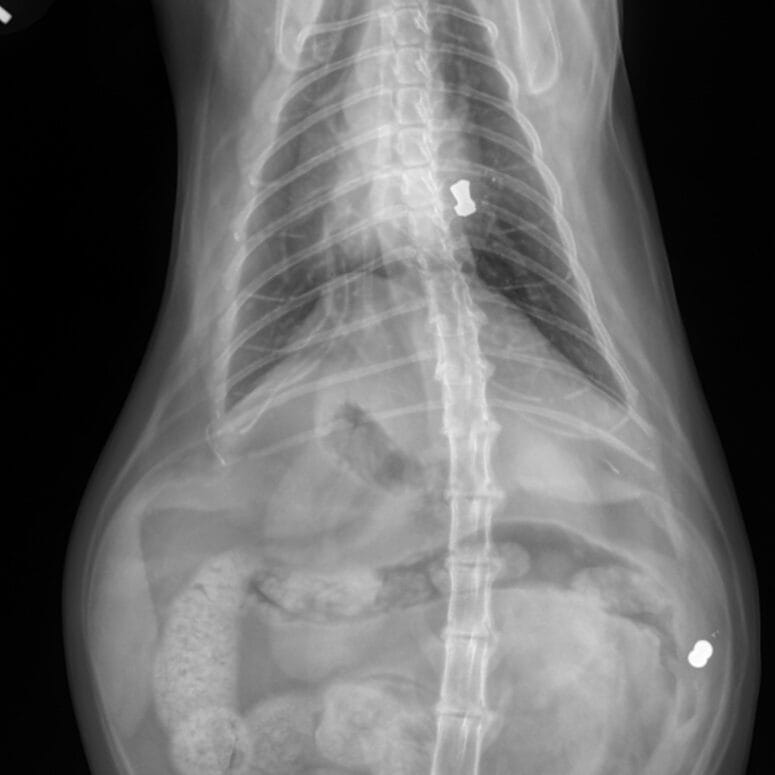

“The vets thought maybe a bone spur had formed or a small piece of bone had broken off,” Chelsea explained.

“But they wanted to do more imaging just to be sure. That’s when they found two BB gun pellets, one lodged in her back leg and another in her chest.”

It was a discovery no pet owner ever expects to hear. Hari’s limp, it turned out, was linked to an old fracture that had healed incorrectly.

The scans also revealed several other fractures in her back legs, all injuries that had occurred long before her adoption.

“The CT scan showed that her right front leg is actually shorter than the left because of that old fracture,” Chelsea said. “When they asked if we knew about her past, I just started crying. I had no idea.”